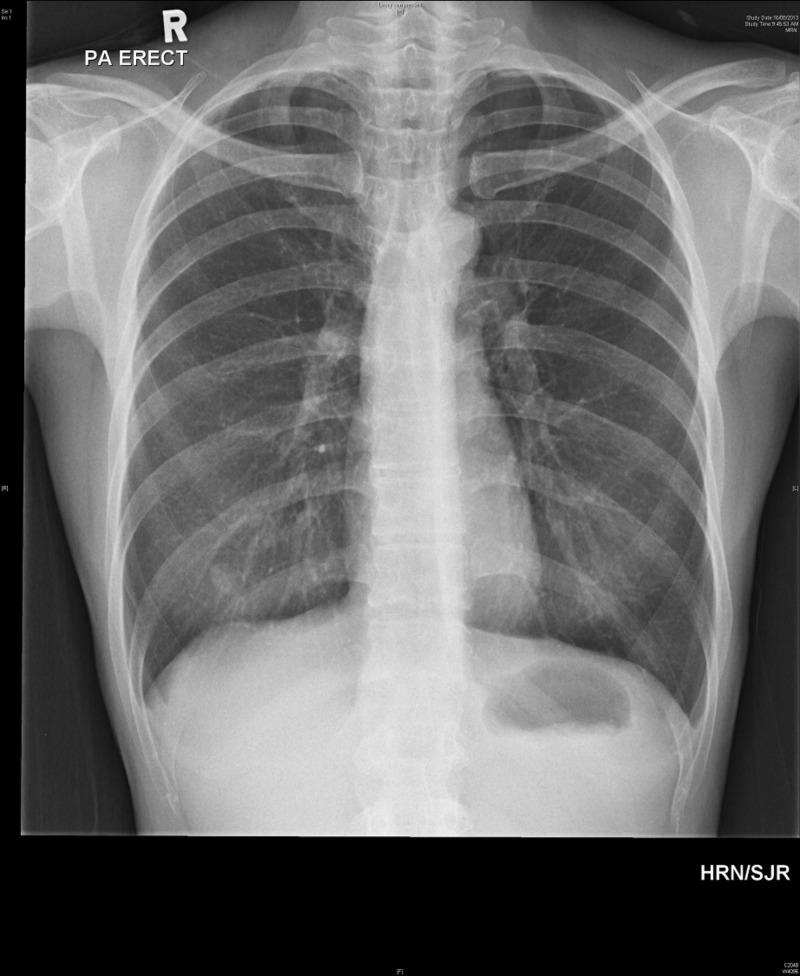

Acupuncture is a common form of therapy involving insertion of fine needles to alleviate nausea and various forms of pain. We describe a case of pneumothorax secondary to acupuncture. A 50-year-old woman presented to the emergency department with right-sided pleuritic chest pain. This was following a history of acupuncture and cupping treatment an hour earlier at a traditional practitioner for long-standing neck pain. On physical examination, the respiratory rate was 22 breaths per minute and her oxygen saturation was 100% on room air. Breath sounds were decreased on the right hemithorax with hyper resonance to percussion. Inspection of her back revealed multiple needling and cupping marks. A chest radiograph revealed a right-sided pneumothorax with an apex-cupola distance of 3.6 cm. She was put on high flow oxygen and a chest tube was inserted into the right chest wall. The patient was admitted. She had radiographic resolution of the pneumothorax four days later and was discharged uneventfully. Follow-up one week later in the clinic showed no radiographic recurrence of the pneumothorax.

针灸是一种常见的治疗方法,通过插入细针来缓解恶心和各种疼痛。我们描述了一例因针灸导致气胸的病例。一名50岁女性因右侧胸膜炎性胸痛被送往急诊科。这是在一小时前于一名传统医生处接受针灸和拔罐治疗以缓解长期颈部疼痛之后出现的。体格检查时,呼吸频率为每分钟22次,在室内空气中氧饱和度为100%。右侧胸廓呼吸音减弱,叩诊呈过清音。检查其背部发现多处针刺和拔罐痕迹。胸部X线片显示右侧气胸,尖 - 圆顶距离为3.6厘米。她接受了高流量吸氧,并在右胸壁插入了胸管。患者入院。四天后气胸在影像学上得到缓解,顺利出院。一周后在诊所随访显示气胸无影像学复发。